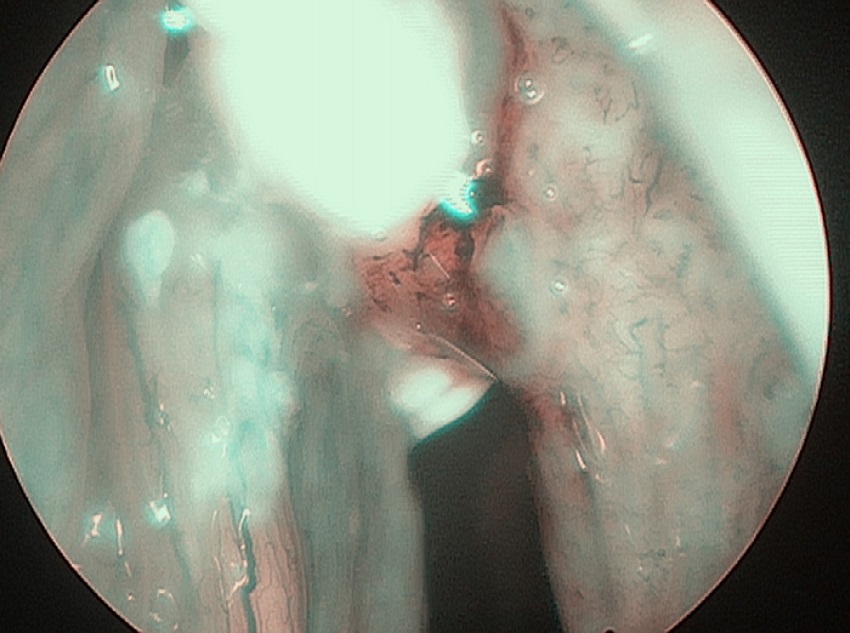

In 6 patients mucosa was suspected only in NBI (Fig. 1), with no such evidence in WL (Fig. 2). In these 6 patients 18/90 (20%) samples were taken. In 5/6 patients 16/18 (88.8%) samples were positive in FS. In 6/18 (33.3%) samples (2 patients) carcinoma, in 10/18 (66.6%) samples (3 patients) severe dysplasia were confirmed. One patient in 2/18 (11.1%) samples had a negative FS.

To summarize, in 6/44 (13.6%) patients NBI allowed to take the FS, so that the diseased mucosa was included into the surgical specimens. Presented analysis showed that sensitivity, specificity and accuracy of WL was 79.5%, 20%, and 71.1% respectively, while NBI corresponding values were: 100%, 0.0%, and 85.7%, respectively.